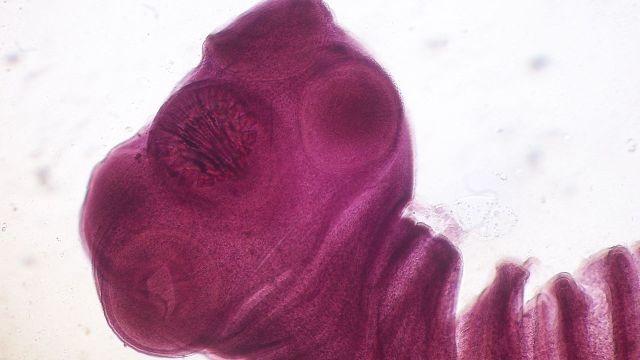

etapas larvales o intermedias de desarrollo de la tenia porcina Sinc

Estos son dos 'Taenia solium' representan las etapas larvales o intermedias de desarrollo de esta tenia porcina. / cdc | dr. George r. Healy, 1973